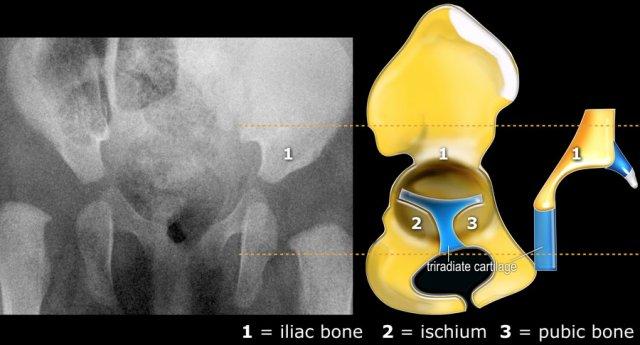

Với siêu âm, chúng ta quan sát các cấu trúc giải phẫu tương tự như trên phim X-quang.

Các hình ảnh siêu âm được thực hiện trên mặt phẳng coronal (hình).

Do đó, phân loại loạn sản khớp háng theo Graf chủ yếu dựa trên hình thái xương chậu, trong đó chúng ta xem xét hình dạng của ổ cối, bờ ổ cối xương và sụn, sụn viền và vị trí của chỏm xương đùi.

Vì siêu âm có ưu điểm là cũng hiển thị được các cấu trúc sụn, chúng ta có thể quan sát mức độ che phủ của chỏm xương đùi bởi sụn ổ cối và sụn viền.

Vì trẻ sơ sinh đang nằm nghiêng nên cấu trúc giải phẫu được hiển thị theo chiều ngang thay vì chiều dọc (hình)

Và đây là cách hình ảnh siêu âm được hiển thị trên màn hình của máy siêu âm